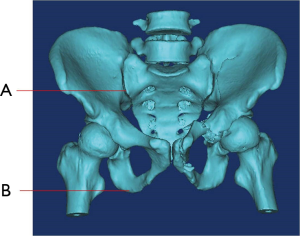

1. What’s name of bone that marked as “B”

- Sacrum

- Pubis

- Ilium

- Ischium

2. What’s name of the joint/symphysis that marked as “A”?

- Sacroiliac joint

- Hip joint

- Pubic symphysis

- Sacrococcygeal symphysis

3. Which bone involves fracture?

- Only the bone of Pubis and Ischium.

- Only the bone of pubis, ischium and sacrum

- Only the bone of pubis, ischium and ilium.

- All the bone of pubis, ischium, sacrum and ilium.

4. Did the fracture involve the following joints?

- None of “Sacroiliac joint” and “Hip joint”.

- Both of “Sacroiliac joint” and “Hip joint”.

- Only “Sacroiliac joint”

- Only “Hip joint”.

5. Did the fracture involve the pubic tubercle?

- Yes

- No